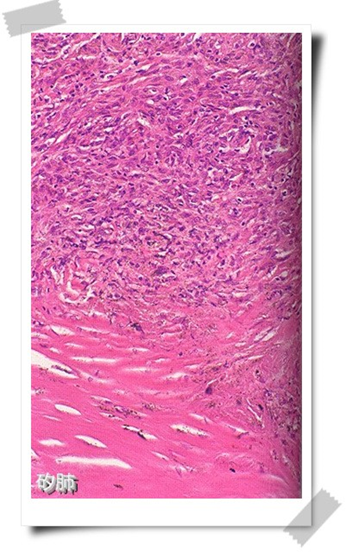

矽肺

矽肺的基本病理改变是矽结节形成和弥漫性间质纤维化,矽结节是矽肺特征性病理改变。矽肺病理形态可分为结节型、弥漫性间质纤维化型、矽性蛋白沉积和团块型。

1.结节型矽肺:由于长期吸入游离二氧化硅含量较高的粉尘而引起的肺组织纤维化,典型病变为矽结节(silicoticnodule)。肉眼观,矽结节稍隆起于肺表面呈半球状,在肺切面多见于胸膜下和肺组织内,大小约为1~5mm。镜下观,可见不同发育阶段和类型的矽结节。早期矽结节胶原纤维细且排列疏松,间有大量尘细胞和成纤维细胞。结节越成熟,胶原纤维越粗大密集,细胞越少,终至胶原纤维发生透明性变,中心管腔受压,成为典型矽结节。典型矽结节横断面以葱头状,外周是多层紧密排列呈同心圆状的胶原纤维,中心或偏侧为一闭塞的小血管或小支气管。有的矽结节以缠绕成团的胶原纤维为核心,周围是呈漩涡状排列的尘细胞、尘粒及纤维性结缔组织。粉尘中游离二氧化硅含量越高,矽结节形成时间越长,结节越成熟,典型。有的矽结节直径虽很小,但很成熟,出现中心钙盐沉着,多见于长期吸入低浓度高游离二氧化硅含量粉尘进展缓慢的病例。淋巴结内也可见矽结节。

典型矽结节似“洋葱头”状结构 典型矽结节(“旋涡状”排列)

矽肺 矽肺